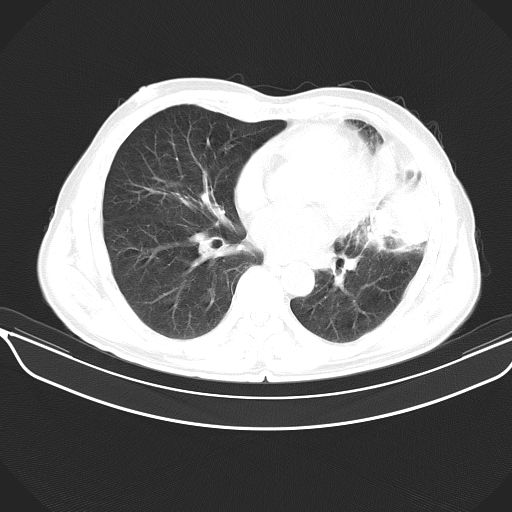

以下是引用心路寻觅在2010-3-1 10:23:00的发言:[br]1、考虑左肺上叶周围型肺癌[br]2、右上肺陈旧性病灶。[br][br][本贴已被 心路寻觅 于 2010-3-1 10:40:18 修改过]

以下是引用shuiyuan在2010-3-1 10:45:00的发言:[br]考虑左肺上叶中心型肺癌伴阻塞型炎症,邻近胸膜受侵。